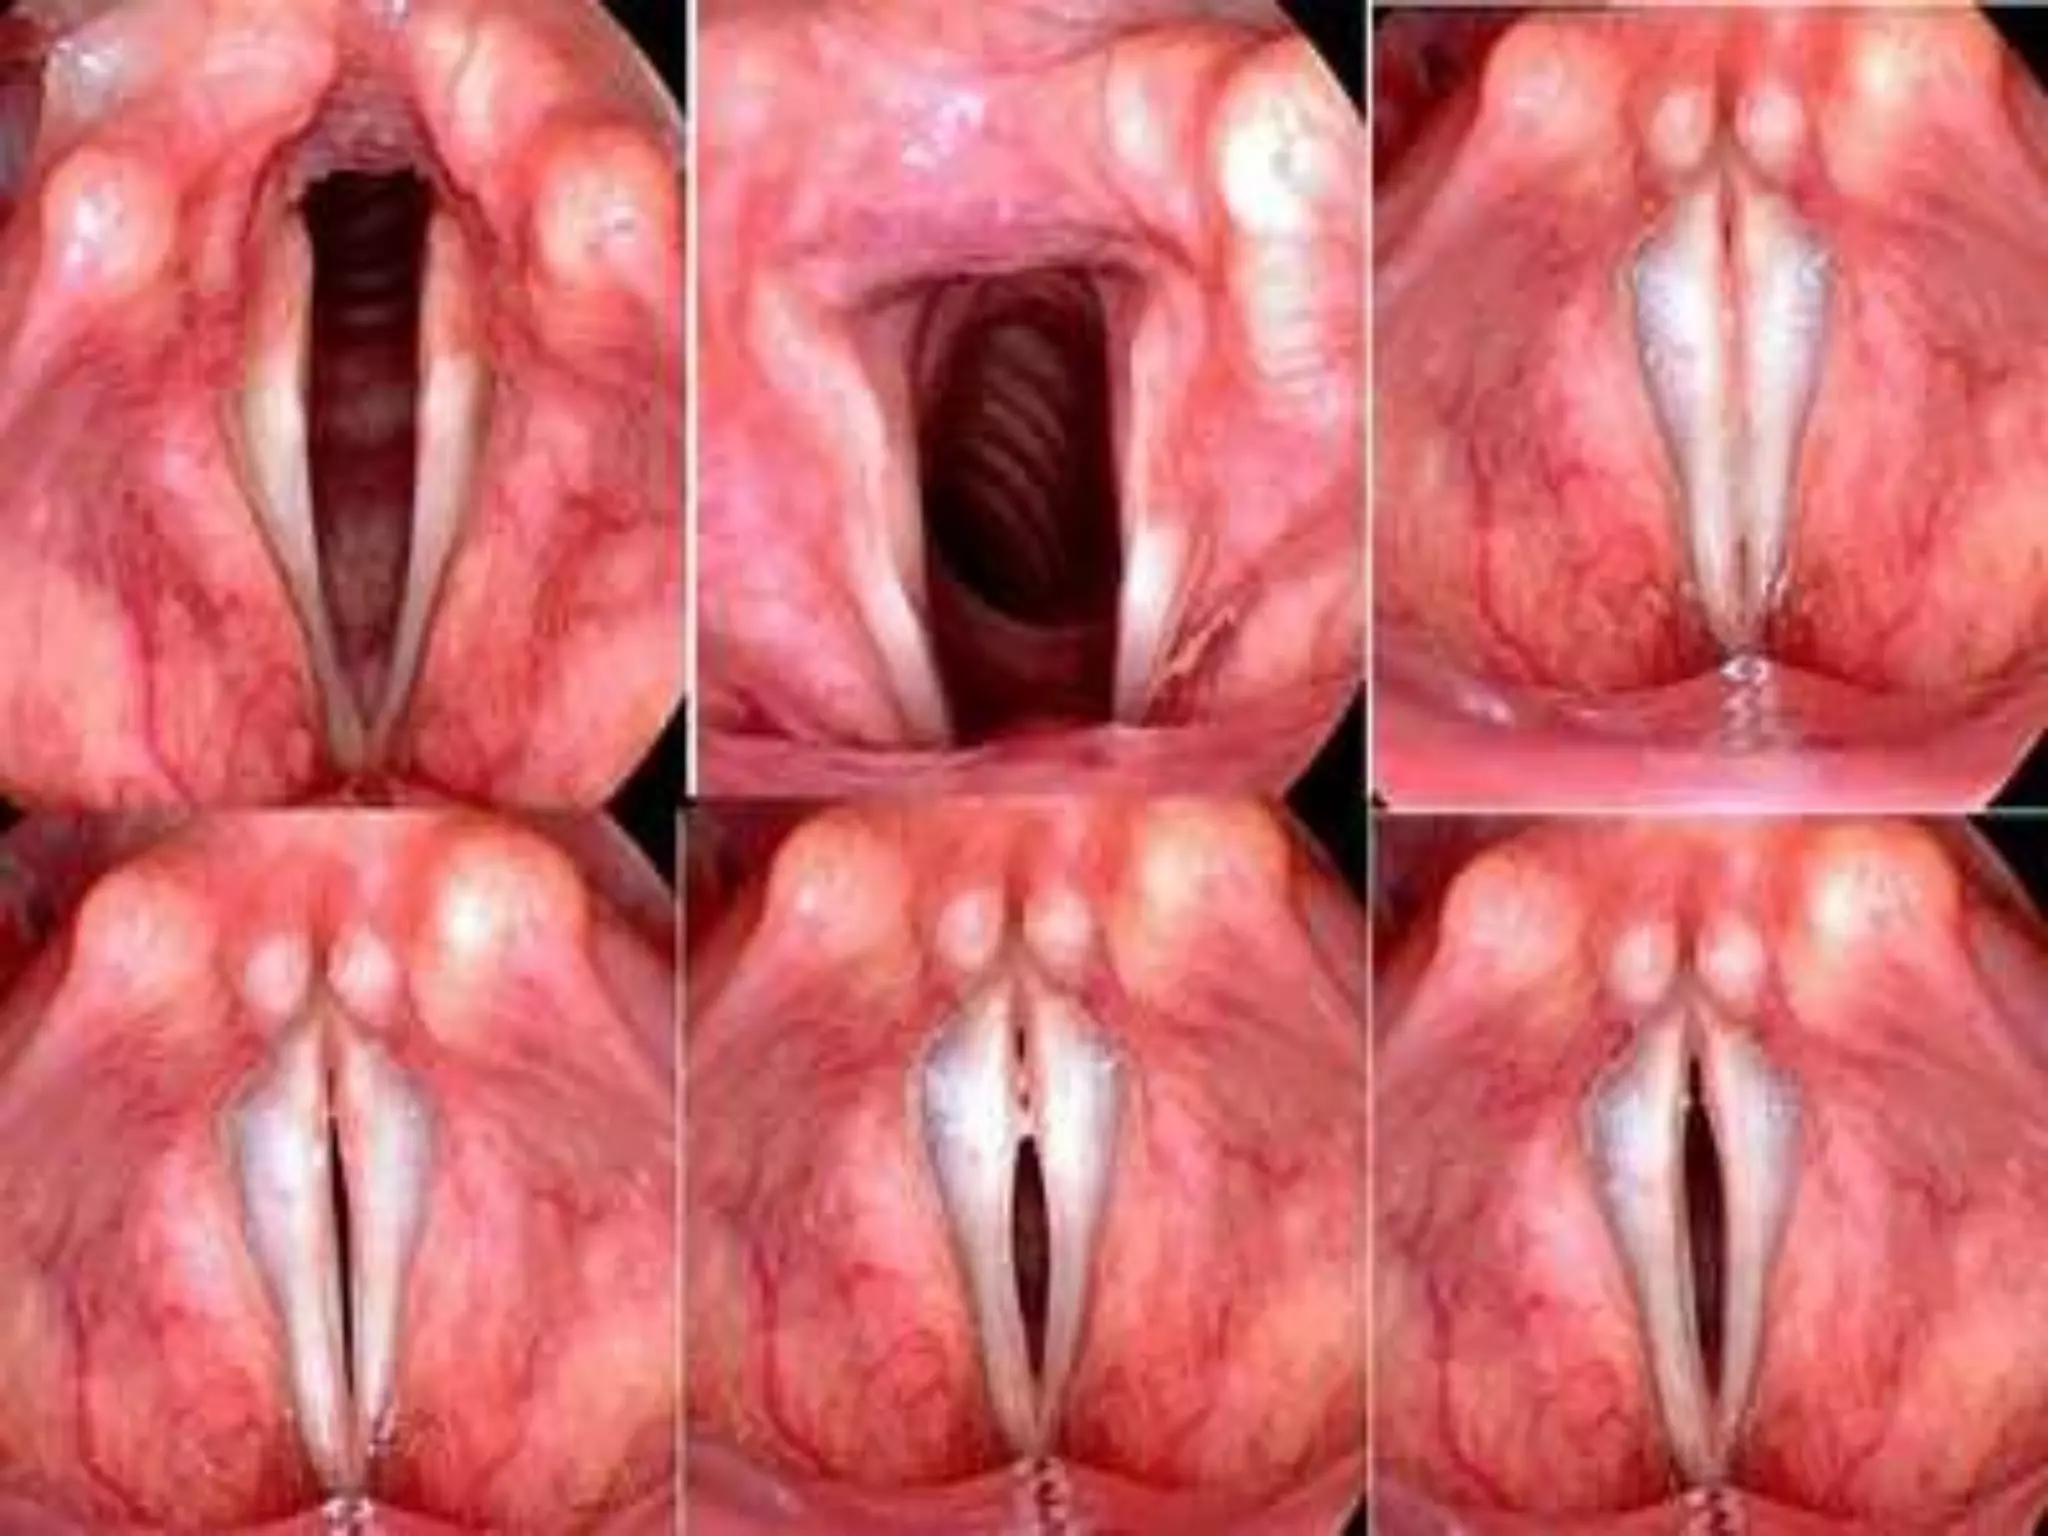

• Na laringe se encontram

as pregas vocais.

Laringe • É umtubo sustentado por peças de cartilagem articuladas, situado na parte superior do pescoço, em continuação à faringe. • Na laringe se encontram as pregas vocais.